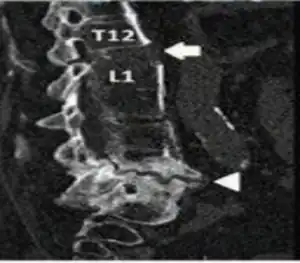

.png.webp)

Inadequately healed chalk stick fracture with sclerotic margins was seen at L4-L5 level arrow head